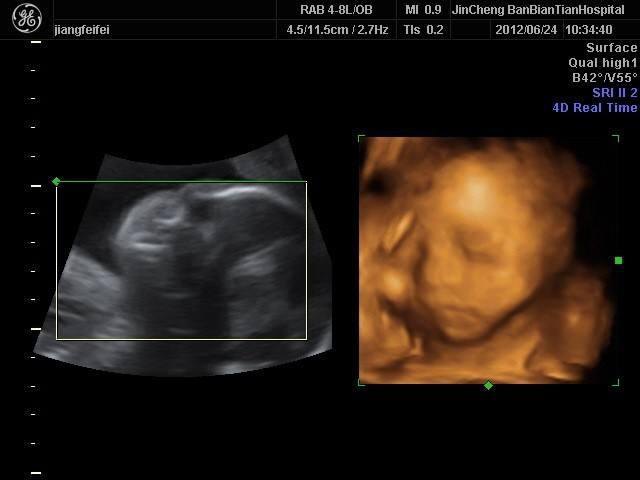

四维彩超是目前比较流行的孕检之一,四维能对胎儿头面部立体成像,可清晰显示胎儿的状态,网上很多四维是女孩但是却生了男孩的案例,那么四维女孩翻盘几率大吗?更多关于生男生女的相关内容尽在孕宝网。

四维一般都是二十四周以后照的,这么大的孕周出错的机会还是比较小的,虽然不是百分之百准确的,但是出错的概率还是会比较少的,大部分情况都是不会出现翻盘的情况,四维超声同其它超声检查相比,可以实时观察人体内部器官的动态运动,也能准确地分辨出胎儿的性别。虽然四维彩超能够看清胎儿的性别,但在检查过程中,为了避免透露胎儿的性别,医生会主动的回避胎儿的性别特征以及下半身,因此最好找熟人的医生做这样才能更准确知道宝宝的性别。